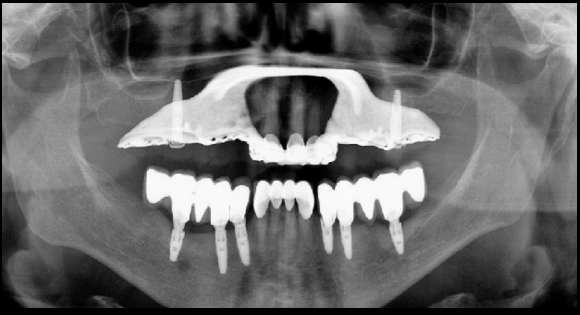

What error (s) do we see here?

A. Head rotated or twisted to right more

B. Head rotated or twisted to the left more

C. Chin too high

D. Chin too low